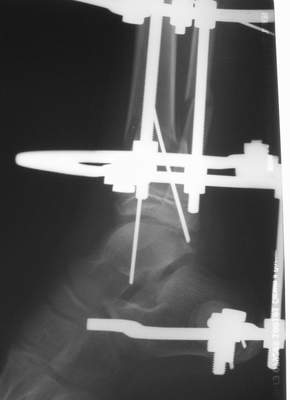

A> Это сросшийся перелом малоберцовой кости. И ложный сустав

A> н\3 б\берцовой кости.

Нашел в комп-ре схожий случай:

1) з/репозиция, 2) фиксация 2 спицами, 3) аппарат, 4) фиксационные

спицы удалены...

А можно было наложить аппарат и по поводу ложного сустава...

По крайней мере не было бы укорочения (пусть и в 2 см)...